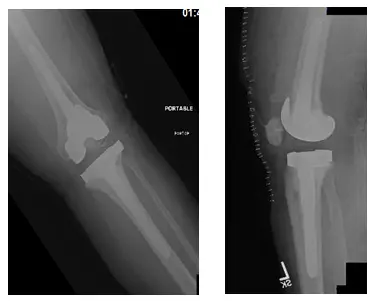

Tibial Stem for a modular tibial tray

The modular tibial stem shown in the image above is used in revision knee surgery. The stem helps to transmit the pressure on the polyethylene bearing distally, thus preventing excessive wear and tear.

Short femoral stem

Modular tibial tray with metal bone augments

The metal augments shown in the image above may be attached to the modular tibial tray to accommodate for bone loss encountered intra-operatively.

Modular femoral revision component

The modular femoral component used in revision knee surgery has an attachment for femoral stem and meta bone augments.